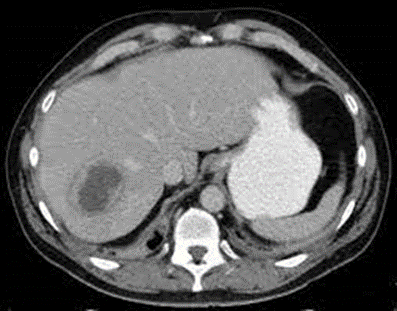

10. Watercress / Fasciola hepatica (liver abscess)